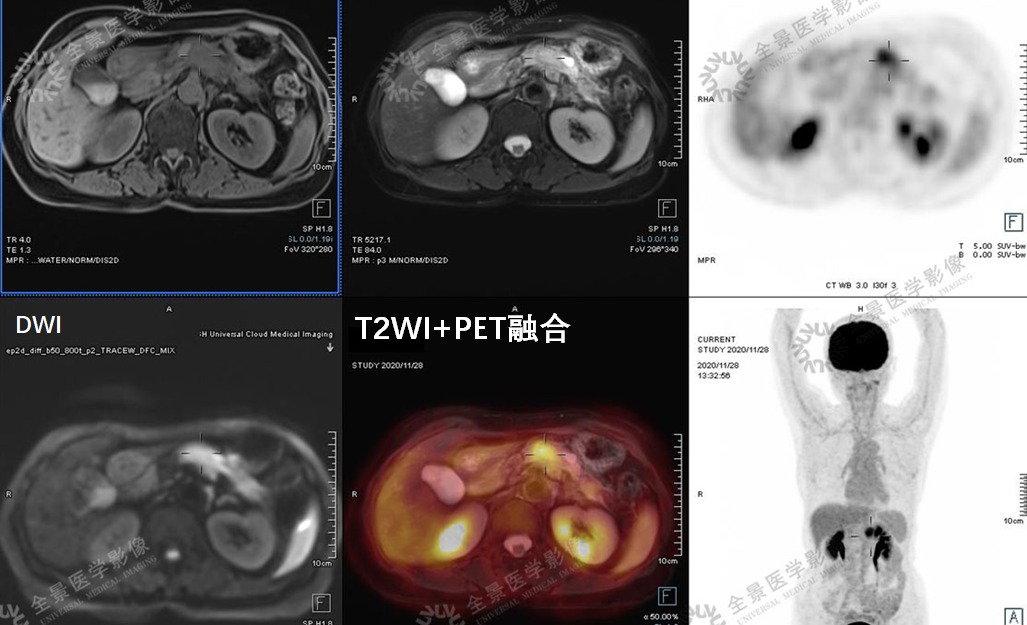

消化系统

案例1 :中年男性,公司体检报告中超声提示肝右叶稍高回声影,结合今年突然消瘦了十几斤,行MR(磁共振)上腹部增强扫描:

表现:肝S5段团片影,增强扫描持续强化。考虑有肿瘤可能性,但无法明确。由于当天肝脏肿瘤指标AFP结果未出,结合已做的腹部彩超和MR增强扫描,考虑肿瘤可能性大。

医生建议他进行全面的PET/CT检查。

PET/CT图像

PET/CT-MR异机融合图像

实验室检查:乙肝阳性,肿瘤标志物:AFP 800+。

结合实验室检查,诊断为肝癌。

目前患者肝癌已切除,术后病理也已证实。

表现:CT显示不清,行PET/CT-MR融合检查,MRI显示清晰,PET提示病灶有轻度FDG摄取,诊断为小肝癌。

案例3 :老年女性,行PET/CT-MR融合检查。

表现:FDG高代谢病变,增强MR病灶主体乏血供、低强化表现。